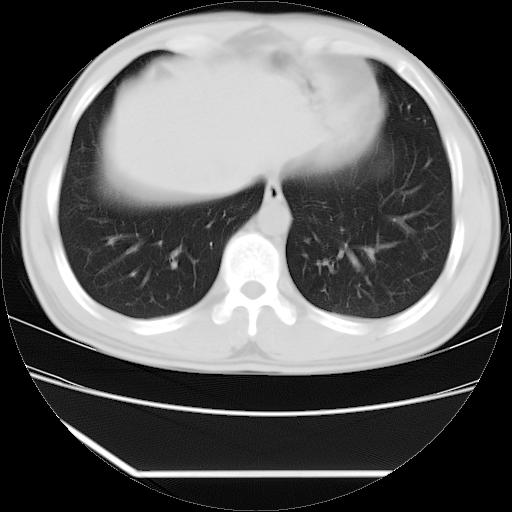

男,38岁,于2009年8月9日晚突发左侧胸痛,今x线提示左下肺阴影,为了明显确诊断,行ct检查,

血常规:嗜酸性细胞增高,单核细胞增高。

病灶发生在下叶,密度均匀,边缘模糊、毛糙,周围血管纹理增强扭曲改变,靠近胸膜处病灶胸膜反应明显。

支持考虑---球形肺炎。

左肺舌叶病变。主体病灶呈类圆形中心密度低,成液化趋势周边班片影分布

考虑肺脓肿

虽然实验室检查支持炎性病变,且病变内有坏死改变(中央呈大片状低密度影),但仍不能掉以轻心,鳞癌也可以有这种影像改变。